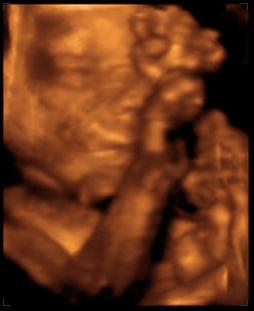

Mindjárt jönnek a 4D képek!!!

Na akkor a 4D képek! Törpike (merthogy neve még változatlanul nincs), fejecskéje 6,71 cm, súlya kb. 920 gr., 1 héttel kisebb mint a kora, így várhatóan augusztus 26-ra leszek újabb időre kiírva, nem aug. 18-ra. Talán a dokim visszaér addigra szabiról, és tudok vele egyezkedni. Szóval összességében jól alakulnak a dolgok. A 4D egyébként irtó jó volt! Most először hallottuk a szívverését is, és nem is tudom szavakba önteni, milyen különös érzés keríti hatalmába az embert ott a félhomályos vizsgálóba, amikor meglátja először a 4D képet. A kezecskéket rendesen, nem csak a csontokat belőle és a halvány körvonalakat. Az orrocskát, a szemecskéjét, még ha csukva volt is, mert a kis drága aludt végig, hiába volt előtte süti meg bármi, nem nagyon hatotta meg :) Az összes kezét, lábát végig az arca előtt tartotta szinte teljesen eltakarva azt, de azért lehetett látni is, na meg olvadozni. Egyébként medence fekvésű jelenleg, vagyis hát a vizsgálatkor, de van még bőven ideje, helye befordulni és mocorogni, úgyhogy nem aggódom. Kértem a dokit, hogy nézze meg a méhlepény-méhszáj távolságát. Kérdezte, mert hogy mélyen volt a lepény? Mondom igen, 12 mm-re. Megmérte, és képzeljétek, a távolság 6!!!!! cm-re nőtt, tehát teljesen felhúzódott, illetve nem kicsit, és már azt is írta a leletre hogy hátsó fali korban érett placenta :) Június 13-án megyek 30 hetes UH-ra a dokimhoz, majd kérem őt is hogy mérje meg, kíváncsi vagyok igazolja-e ezt, és hogy akkor nincs akadálya (legalábbis emiatt) a spontán szülésnek.

Férjecském majdnem elsírta magát a meghatottságtól a vizsgálat elején még (ezt utána mondta), és egyébként azóta is 10 centivel közlekedik a föld fölött, láthatóan eufórikus állapotban van, ami szűnni nem akar, nagyon imádnivaló :) Mondjuk ha a másik nem lenne, akkor ugyanez, de igaziból más most a kapcsolat, én is így érzem. Személyesebb lett a baba iránti szeretetünk, és amikor mentünk az UH után az utcán, olyan más volt. Mintha kivilágosodott volna minden, pedig viharos esős idő volt, és az emberek is mások lettek volna, én nem is tudom, nagyon jó érzés volt :)

Jól van, nem csigázom tovább a kíváncsiságotokat. Szerintem nem kell hozzá magyarázat, magatoktól is látni fogjátok a lényeget ;)